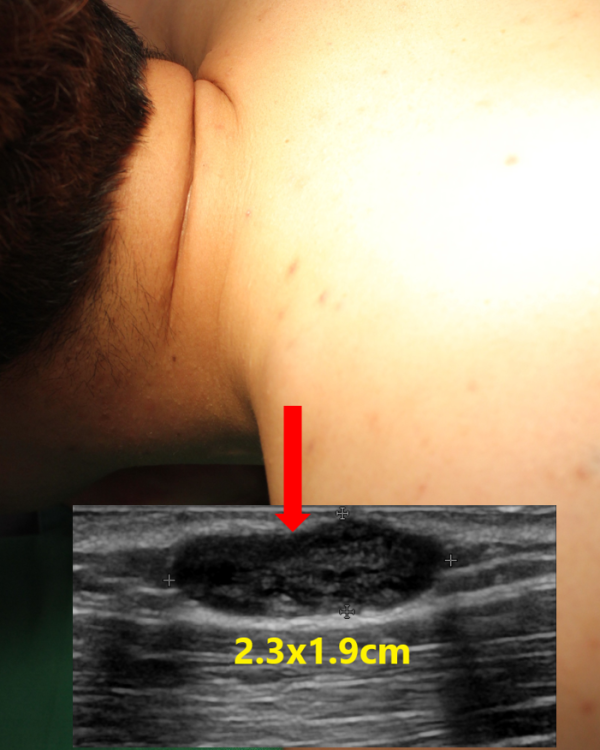

진찰상 왼쪽 어깨에 대략 2cm 크기의 단단한 혹이 만져졌으나 통증이나 압통과 같은 염증을 시사하는 소견은 없었습니다.

혹의 정확한 양상, 크기, 피부로 부터의 깊이, 그리고 염증 소견 등이 있는지 등을 확인하기 위해 초음파 검사를 시행하였습니다.

초음파상 가로x세로의 길이가 약 2.3x1.9cm 크기의 표피낭종으로 확인되었으며 비교적 피부로 부터 가까웠으며 다행히 고름집과 같은 염증소견은 동반되지 않았습니다.